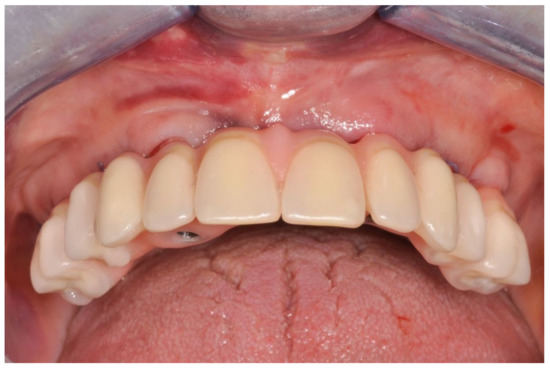

Figure 6.

Definitive prosthesis with cantilevers after 7 years of use.

Figure 7.

Occlusal view of definitive prosthesis after 7 years of use.